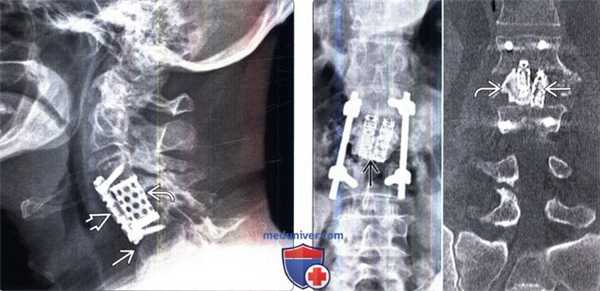

(Слева) Рентгенография в боковой проекции: случай взрывного перелома L2. Пациенту выполнена корпорэктомия и замещение тела позвонка телескопическим кейджем Synex и двусторонняя транспедикулярная стабилизация L1-L3. Задачами хирургического вмешательства при подобных повреждениях являются декомпрессия нервных образований, восстановление высоты тела позвонка, коррекция угловой деформации и стабилизация позвоночного столба.

(Справа) Рентгенография в прямой проекции: визуализируются ТК и боковая стабилизирующая конструкция, которые вкупе позволили добиться эффективной дистракции и восстановления высоты передней колонны, а также снизить стрессовые нагрузки, приходящие на задний транспедикулярный фиксатор. (Слева) Рентгенография шейного отдела позвоночника в боковой проекции: случай корпорэктомии С4 с замещением тела позвонка кейджем и стабилизацией С3-С5 сегмента вентральной пластиной. Подобные сетчатые кейджи выбираются исходя из размеров замыкательных пластинок и высоты дефекта. На этом снимке видны признаки некоторого коллапса тела С5 с проседанием в дефект пластины и кейджа.

(Справа) На рентгенограмме в прямой проекции и фронтальном КТ-срезе визуализируются парные кейджи Pyramesh, использованные для реконструкции коллабированного тела L2 позвонка. Вокруг кейджей визуализируется метилметакрилат.

(Слева) Рентгенография шейного отдела позвоночника в боковой проекции: случай корпорэктомии С4 с замещением тела позвонка кейджем и стабилизацией С3-С5 сегмента вентральной пластиной. Подобные сетчатые кейджи выбираются исходя из размеров замыкательных пластинок и высоты дефекта. На этом снимке видны признаки некоторого коллапса тела С5 с проседанием в дефект пластины и кейджа.